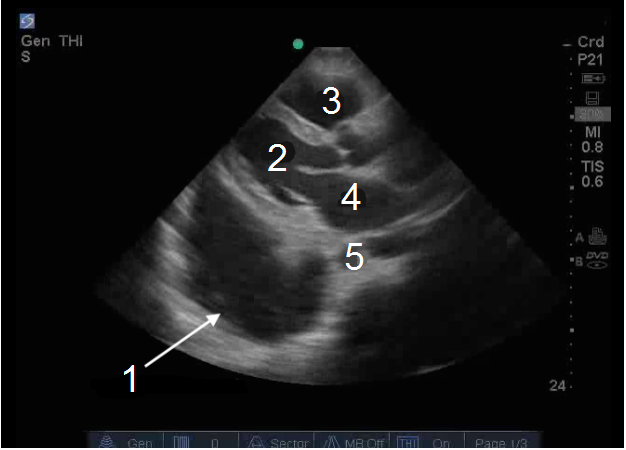

Heart Parasternal Long Axis (PLAX) Pleural Fluid 1 Image

1. Large Pleural Effusion (Fluid)

2. Left Ventricle (LV)

3. Right Ventricle (RV)

4. Left Atrium (LA)

5. Aorta (Ao)